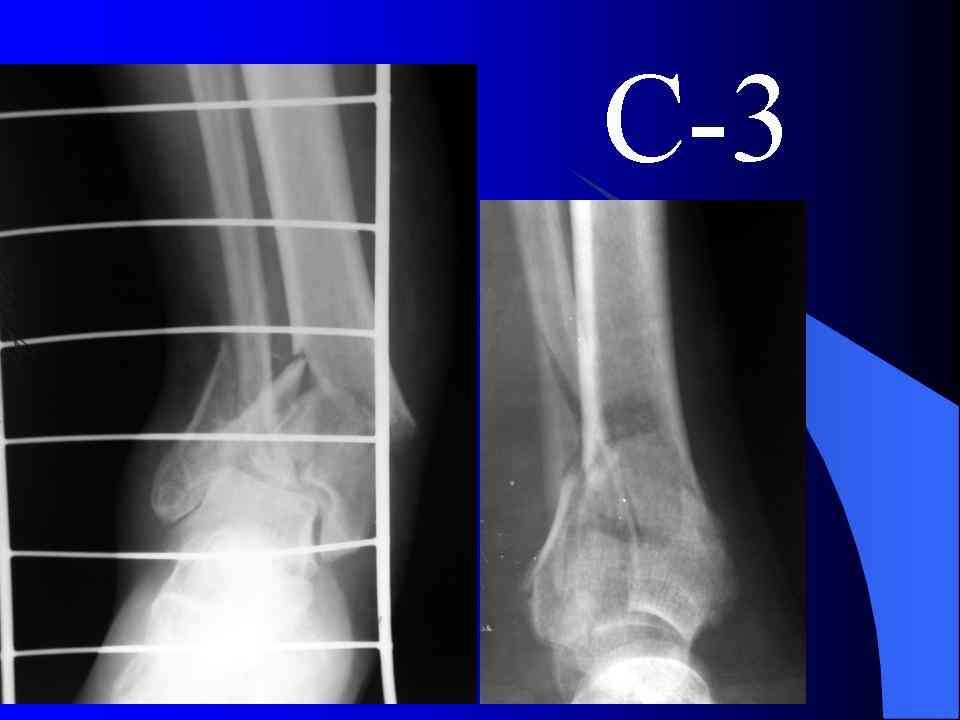

Это типичный перелом пилона, который надп лечить только открыто.Извини те что опоздал к обсуждению, но даже если вы уже оперировали больного по Илизарову это даже лучше.Посылаю картинки.

Посмотрим вроде прошло если понравится напишите расскажу как это сделать.По принципам АО кстати при поступлении сначала восстанавливают длину малоберцовой кости фиксируют пластиной 1/3 трубки потом накладывают аппарат наружной фиксации и через 7-10 дней открыто восстанавливают большеберцовую кость.С уважением Дрягин

На рентгенограммах типичный перелом пилона по типу С-3. есть опыт до 100 открытых опреаций у нас в клинике. 20 примерно в год. Принцип один -все внутрисуставные переломы нуждаются в открытой репозиции и внутренней стабильной фиксации. При поступлении КТ не надо, так как получается только нагромождение костей. Истинной картины нет. Главное восстановить длину малоберцовой кости - это ключ к успеху. При поступлении меньше всего надо думать о сосудистых расстройствах, т.к. сама операция и репозиция даже сначала частичная даёт улучшение сосудитых нарушений. Причём очень быстро. Операция в 2этапа. При поступлении доступ позади наружной лодыжки, причём обязательно. После этого репозиция малоберцовой кости и фиксация пластиной 1/3 трубки под винт 3,5. Дренаж и любой аппарат наружной фиксации. Затем после спадения отёка на 5-7-10 день аппрат снимается и дугообразный разрез спереди от медиальной лодыжки 10-12 см. Главной чтобы расстояние между 1 и вторым разрезом было не меньше 7-8 см. Тогда не будет некрозов лоскутов. Таранная кость используется как матрица на неё укладываются отломки и фиксируются пицами. Ренг-контроль. Отломки лежат все отдельно, но ничего не высыпется. При переломах С-3 всегда нужна костная пластика (из крыла). Фиксация пластиной лист клевера простой или LCP. Гипс не нужен. Дренаж до 48 часов. Операция длится 3-4 часа обязательно без жгута. Посылаю примерно такой же случай.